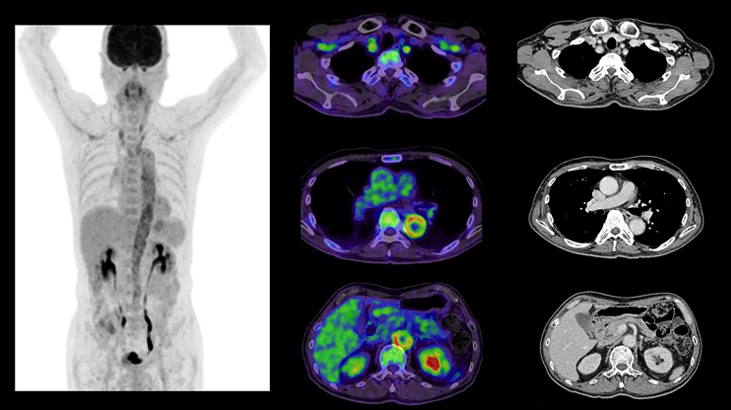

Servicio de PET/CT de Alta Precisión con Siemens Biograph Trinion

Última tecnología para un diagnóstico más preciso.

Imágenes moleculares que permiten un diagnóstico avanzado en:

ONCOLOGÍA

CARDIOLOGÍA

NEUROLOGÍA

¿Qué es un PET/CT?

La Tomografía por Emisión de Positrones (PET) combinada con la Tomografía

Computarizada (CT) es la técnica más avanzada para evaluar la actividad metabólica y la anatomía de órganos y tejidos en una sola exploración.

Permite detectar enfermedades en fases tempranas, monitorizar tratamientos y planificar intervenciones de manera segura y precisa.